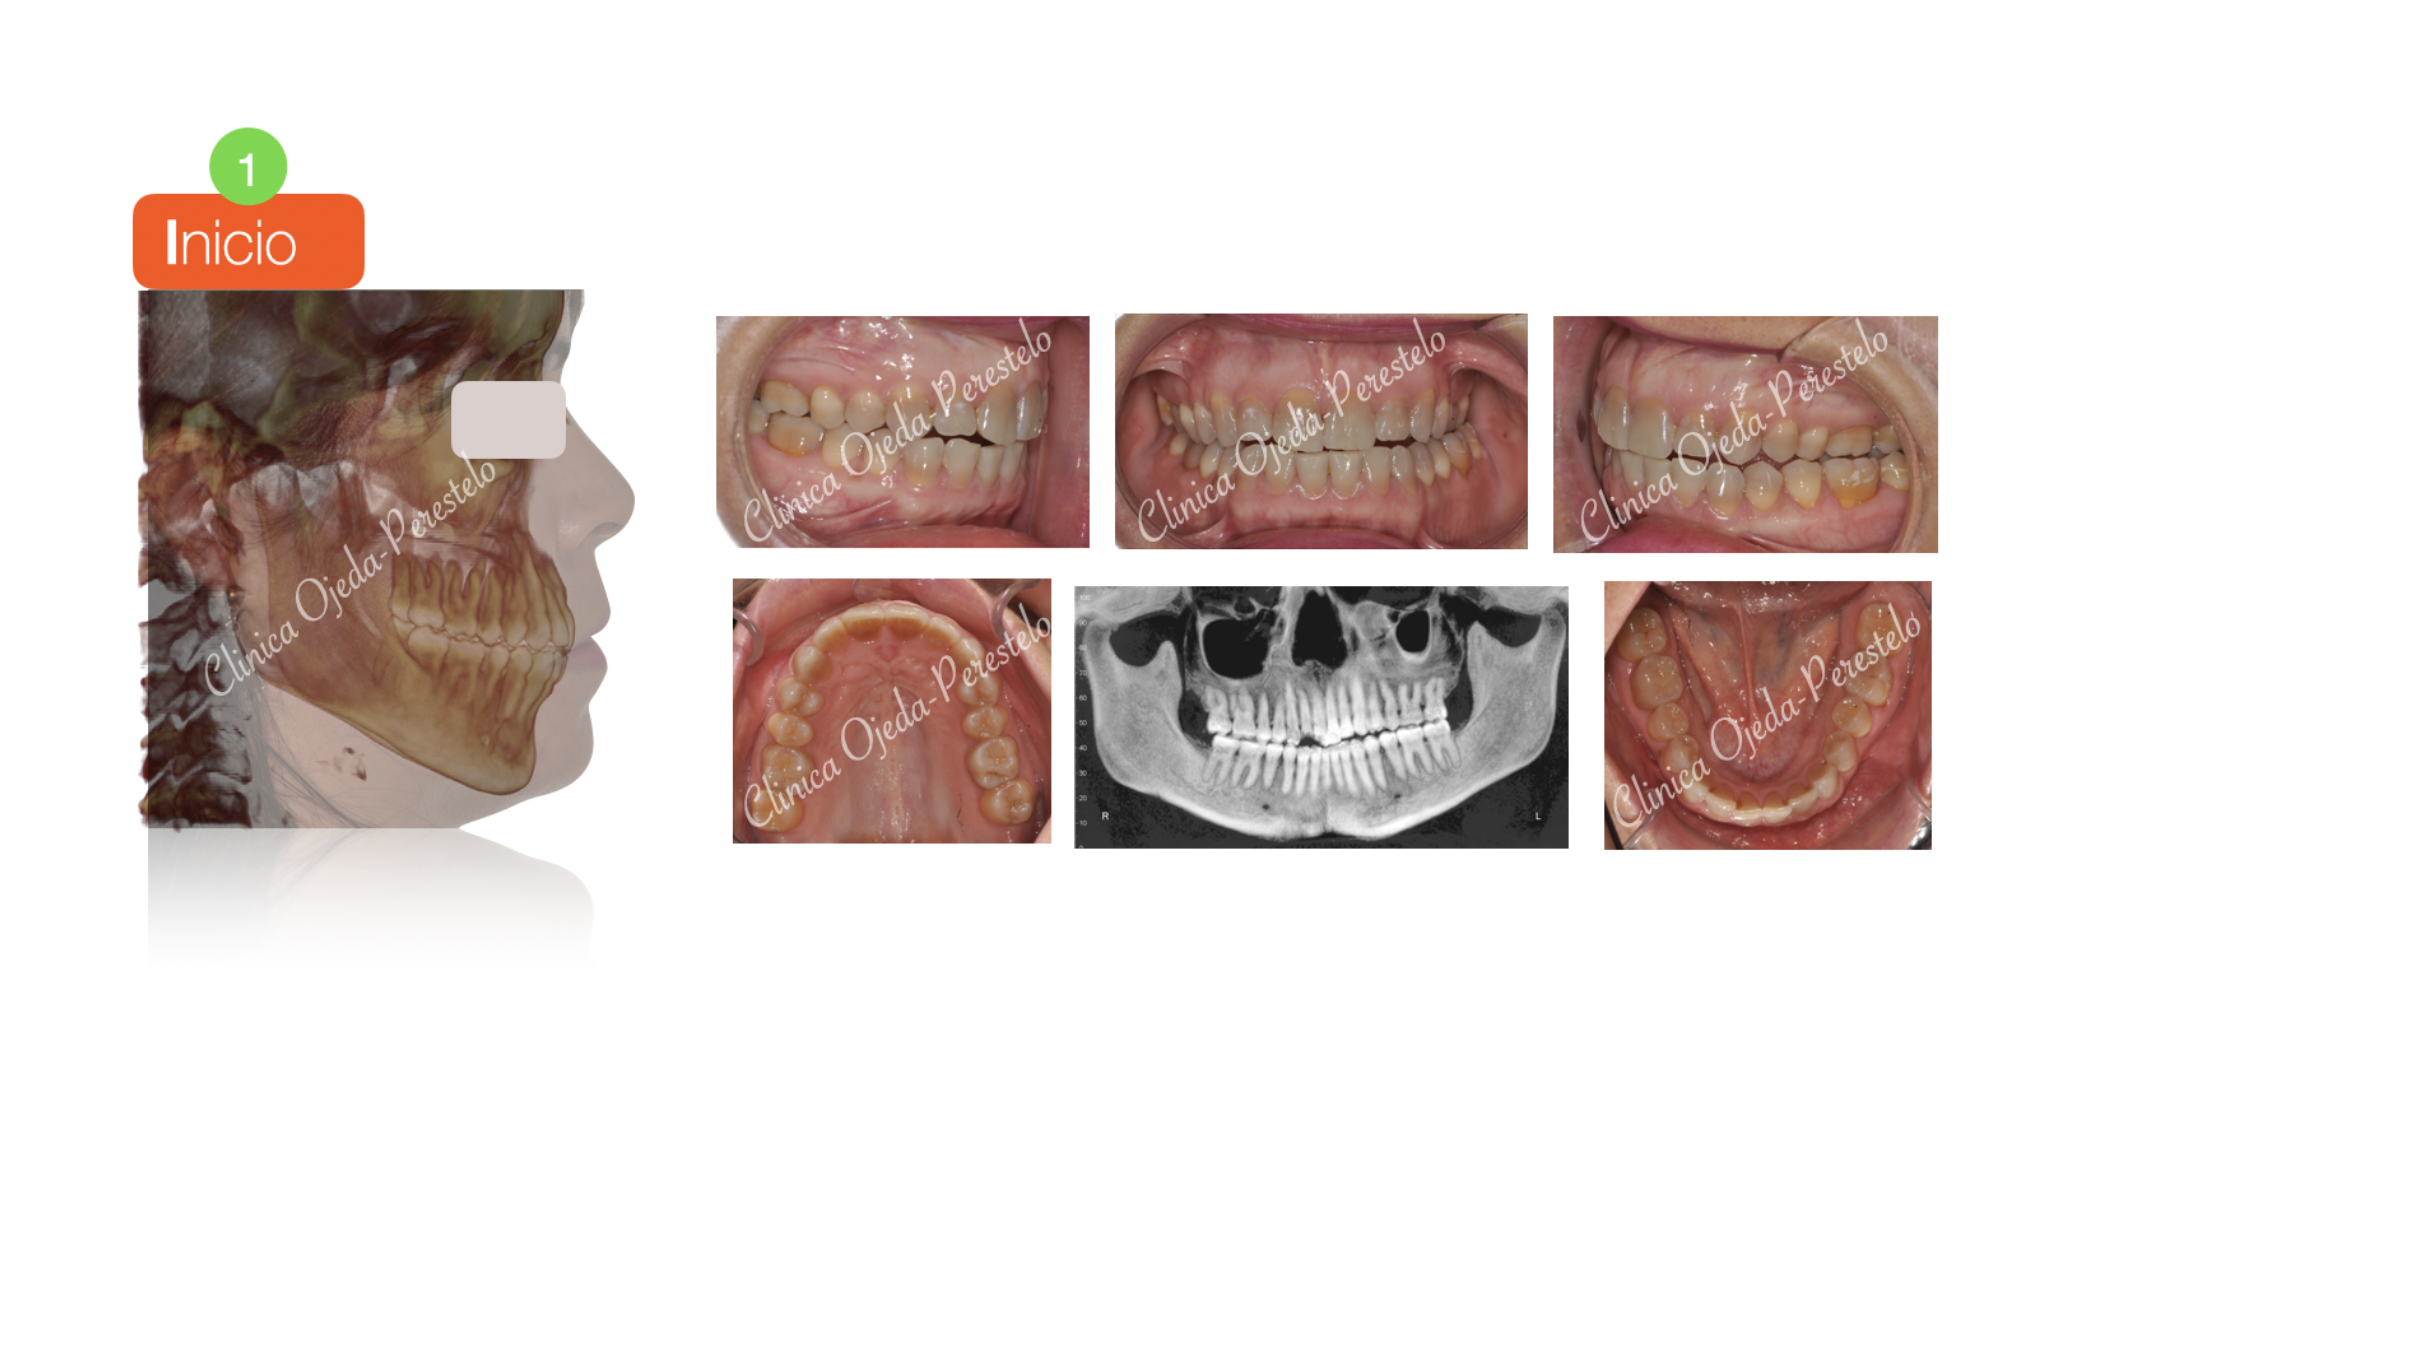

Mordida Cruzada con dolor Craneofacial

Presentamos este caso con mordida cruzada e inestabilidad oclusal que le ocasionaba trastornos y dolores craneofaciales. La paciente ha llevado Microtornillos a efectos de mejorar la inclinación del plano de mordida combinandolo con alineadores y elásticos inntermaxilares.

Finalmente quisiéramos destacar la mejora de la sonrisa, el centrado de las lineas medias, la correcta articulación dentaria además de la desaparición de toda la sintomatología dolorosa a nivel articular y muscular.

El objetivo se ha alcanzado con 56 alineadores superiores y  42 alineadores inferiores con cambio semanal. Le hemos realizado un masking dental en algunas piezas con la idea de dotarle de una oclusión más firme y una mejor estética dental a la paciente.(Bioestética aditiva)